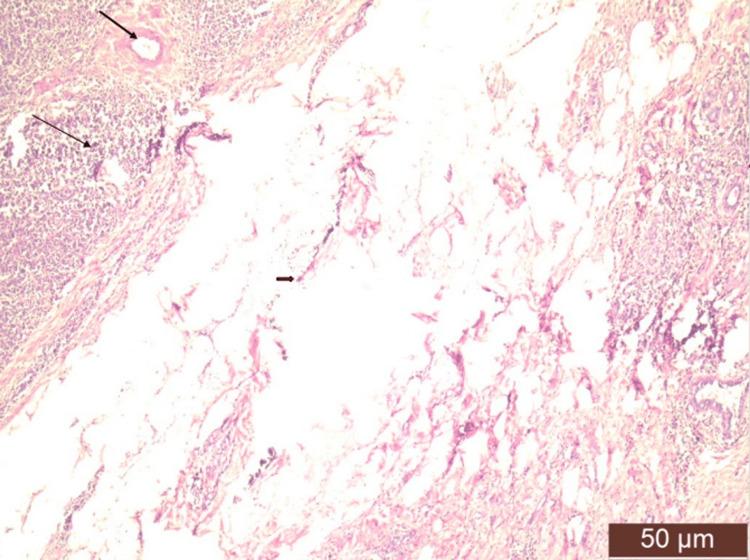

Solitary plasmacytoma of the breast is an extremely rare neoplastic entity characterized by the localized proliferation of neoplastic plasma cells within the breast tissue that requires careful consideration due to its clinical and radiological resemblance to more common breast malignancies. While plasmacytomas are typically associated with multiple myeloma (MM), primary involvement of the breast as a solitary lesion is exceptionally rare. In this report, we present a case of solitary plasmacytoma of the breast in a 55-year-old female patient who presented with a palpable breast mass and no signs of systemic multiple myeloma. Our objective is to discuss the clinical presentation, radiological features, and histopathological findings and highlight the importance of comprehensive diagnostic workup and management planning for solitary plasmacytomas of the breast.